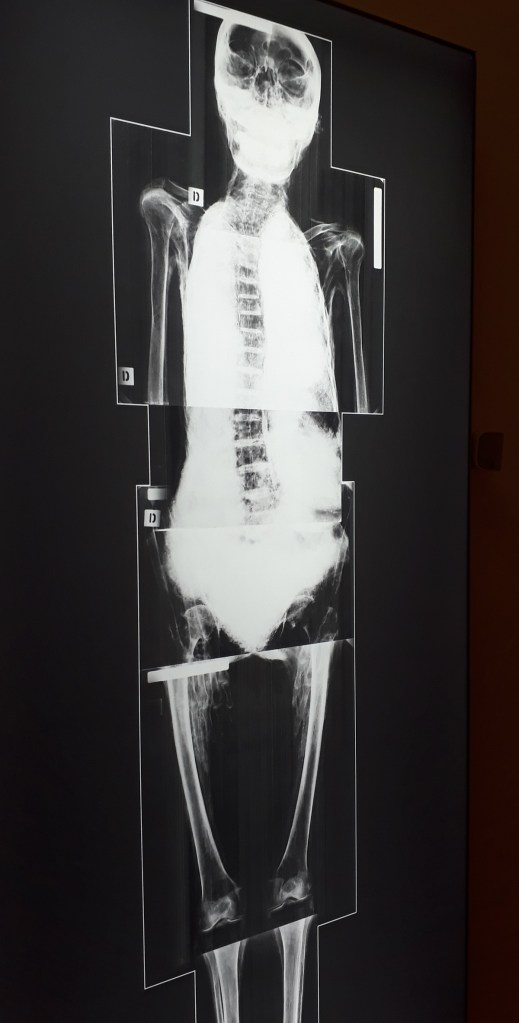

Je l’ai découvert récemment : le musée Granet a une grande collection d’art égyptien ancien. Bas reliefs, stèles, sculptures, amulettes et surtout deux momies, une d’un varan du Nil, et une d’une femme sont visibles à l’exposition Pharaon, Osiris et la momie. Certaines pièces étaient prêtées par d’autres musées.